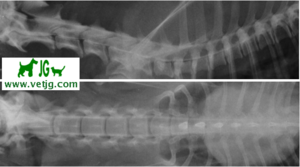

Radiografía con contrastes: mielografía por cisterna magna

RADIOGRAFÍA